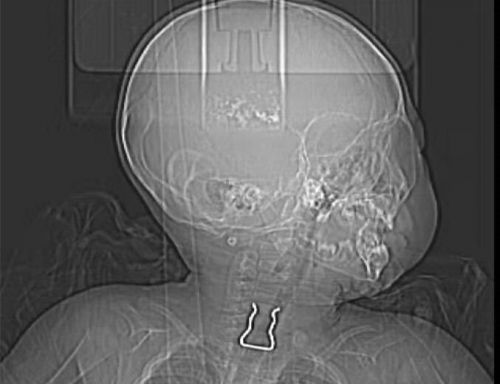

x光片上可以清楚地看到金属异物位于食道入口处。

取出的铁钩约2×3cm大小。

这一系列异常举动让彭女士怀疑孩子是不是吞了什么东西进去,立即询问大女儿得知,弟弟刚才打开电视机下面的抽屉在玩。彭女士赶紧翻看抽屉里的物品,发现一个塑料衣夹被分成两半,其中的铁钩不见了踪影。彭女士怀疑铁钩被儿子吞了下去,赶紧带他来到捷克论坛 耳鼻喉头颈外科门诊就诊。王巍毅主任医师查看CT片发现,一个∪形金属异物卡在孩子的食道入口处,必须手术取出。